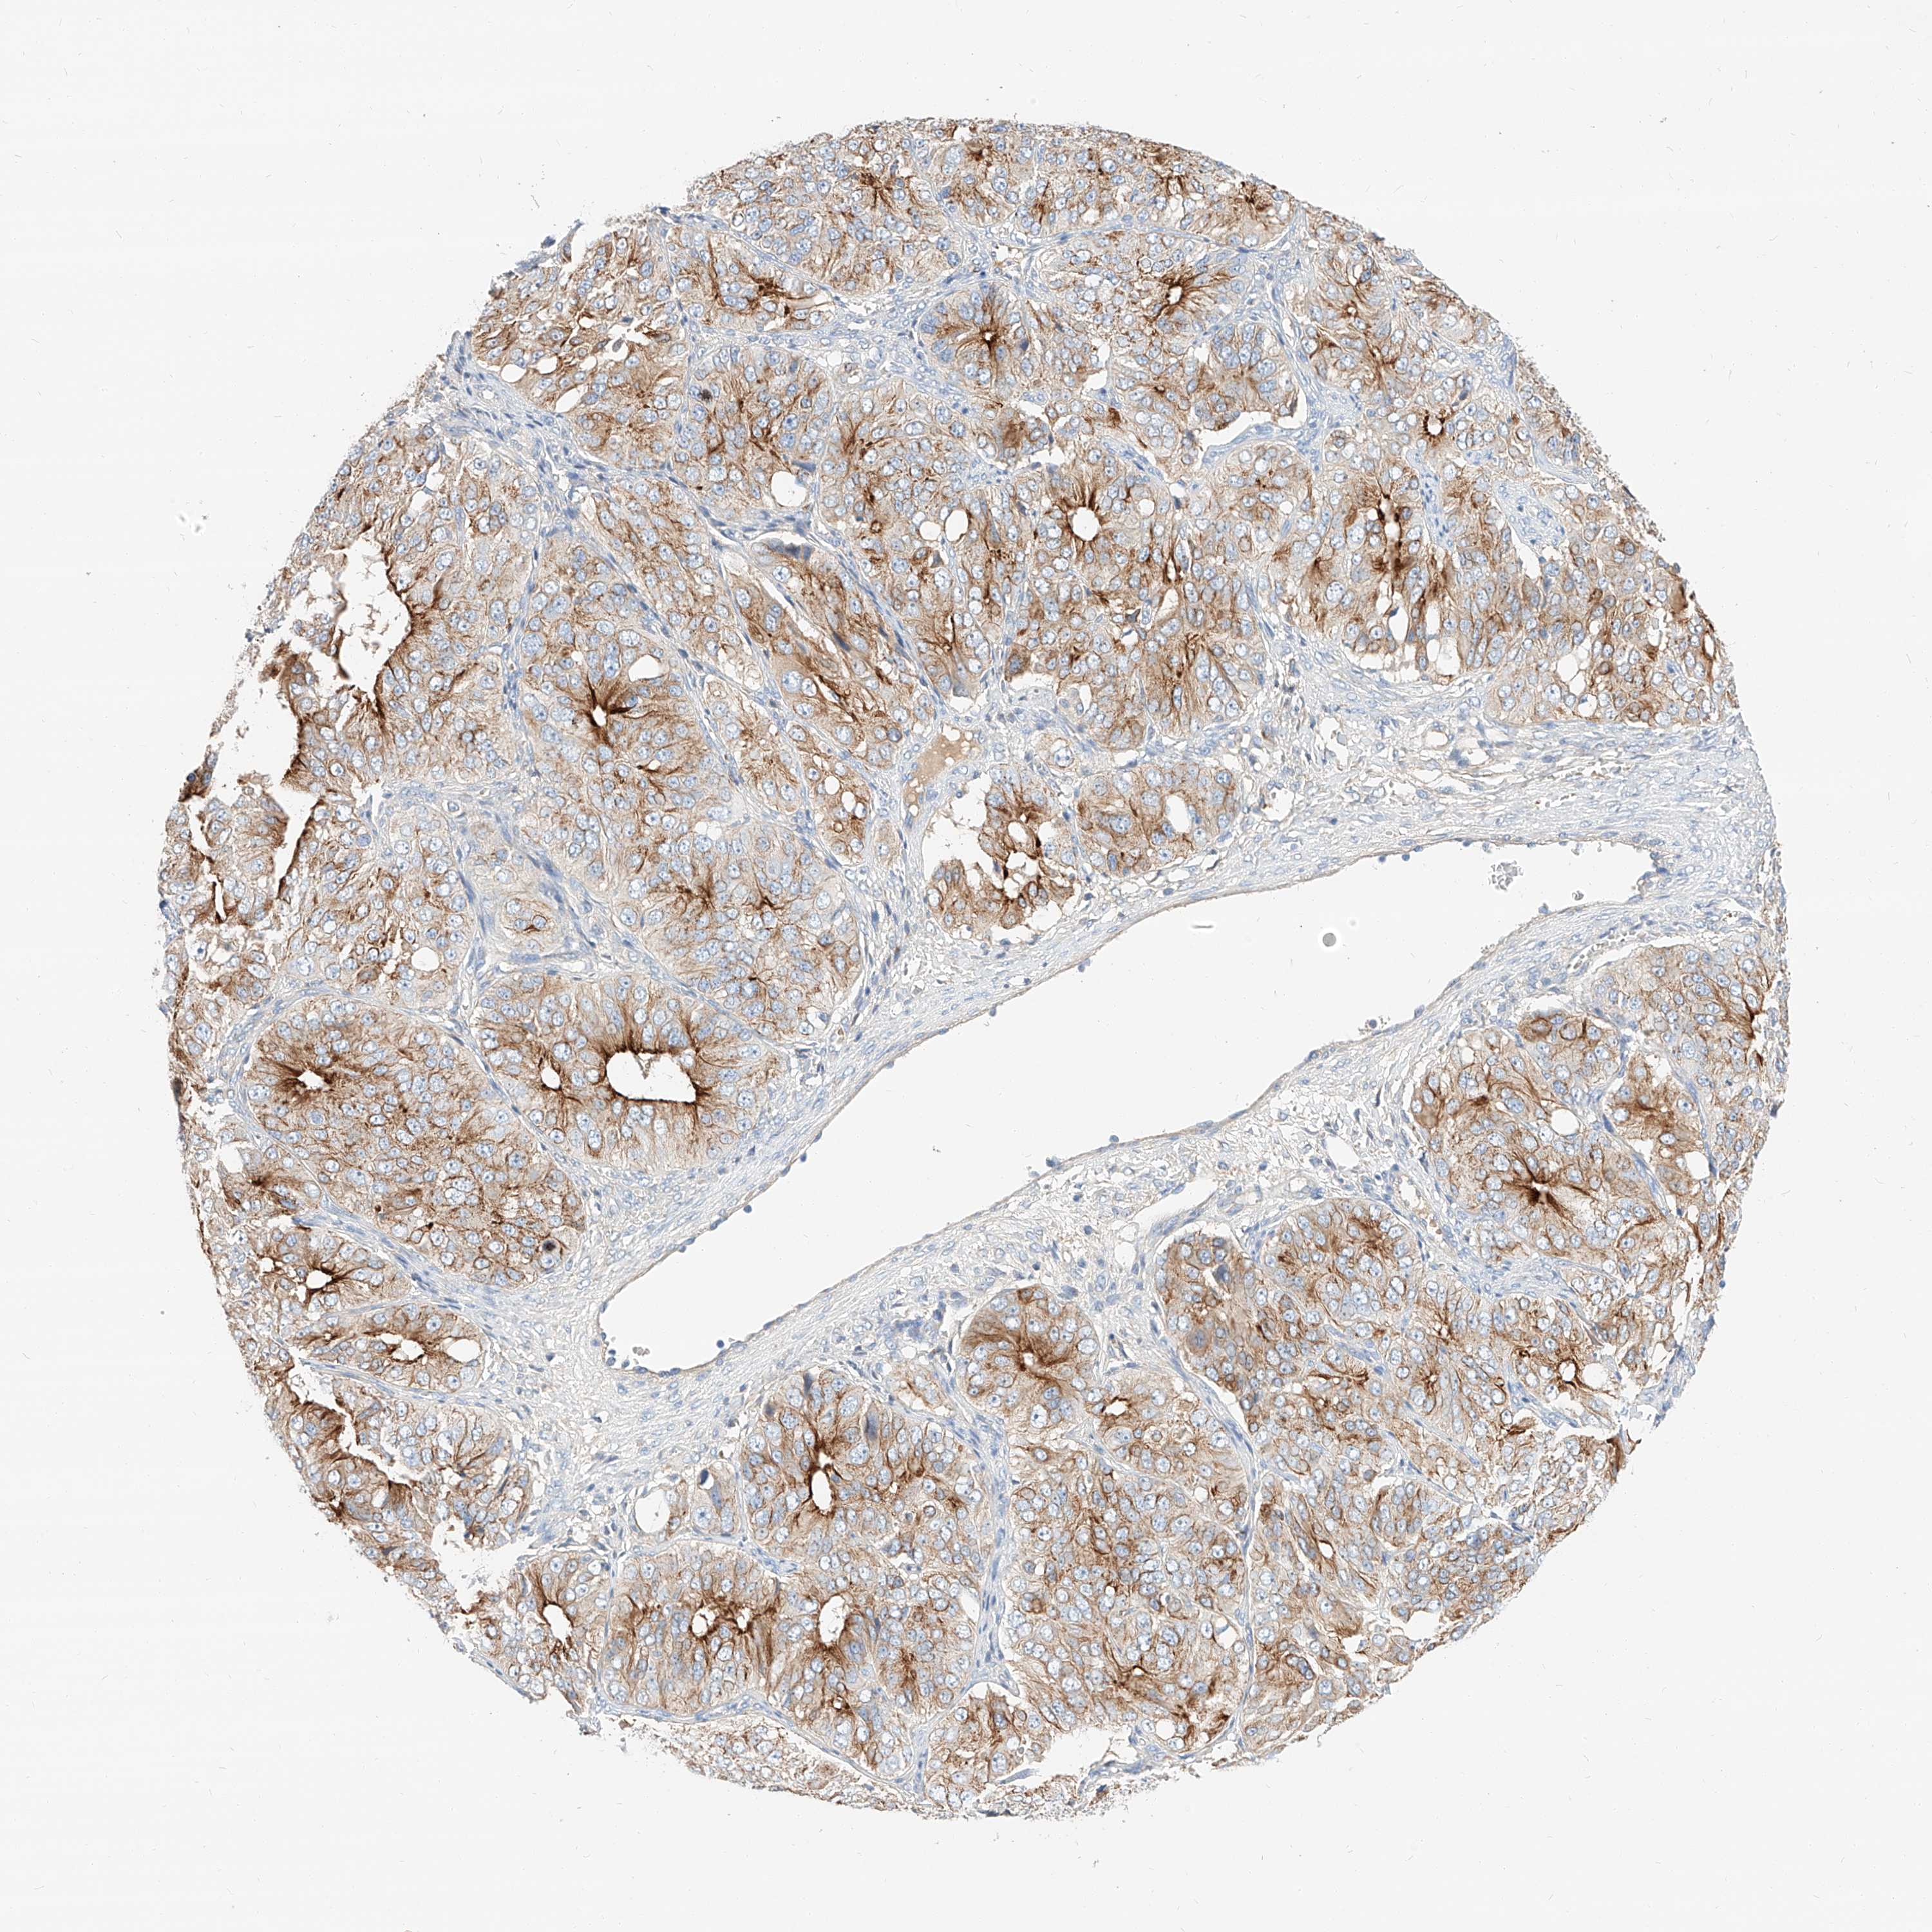

OVARIAN CANCER - Protein expressioni

A mouse-over function shows sample information and annotation data. Click on an image to view it in a full screen mode. Samples can be filtered based on level of antibody staining by selecting one or several of the following categories: high, medium, low and not detected. The assay and annotation is described here.

Note that samples used for immunohistochemistry by the Human Protein Atlas do not correspond to samples in the TCGA dataset.

Antibody stainingi

Antibody staining in the annotated cell types in the current human tissue is reported as not detected, low, medium, or high, based on conventional immunohistochemistry profiling in selected tissues. This score is based on the combination of the staining intensity and fraction of stained cells.

Each image is clickable and will lead to virtual microscopy that enables deeper exploration of all samples and also displays staining intensity scores, fraction scores and subcellular localization as well as patient and tissue information for each sample.

Antibody HPA029712

Antibody HPA029713

Cystadenocarcinoma, serous, NOS

Carcinoma, endometroid

Cystadenocarcinoma, mucinous, NOS

Carcinoma, NOS